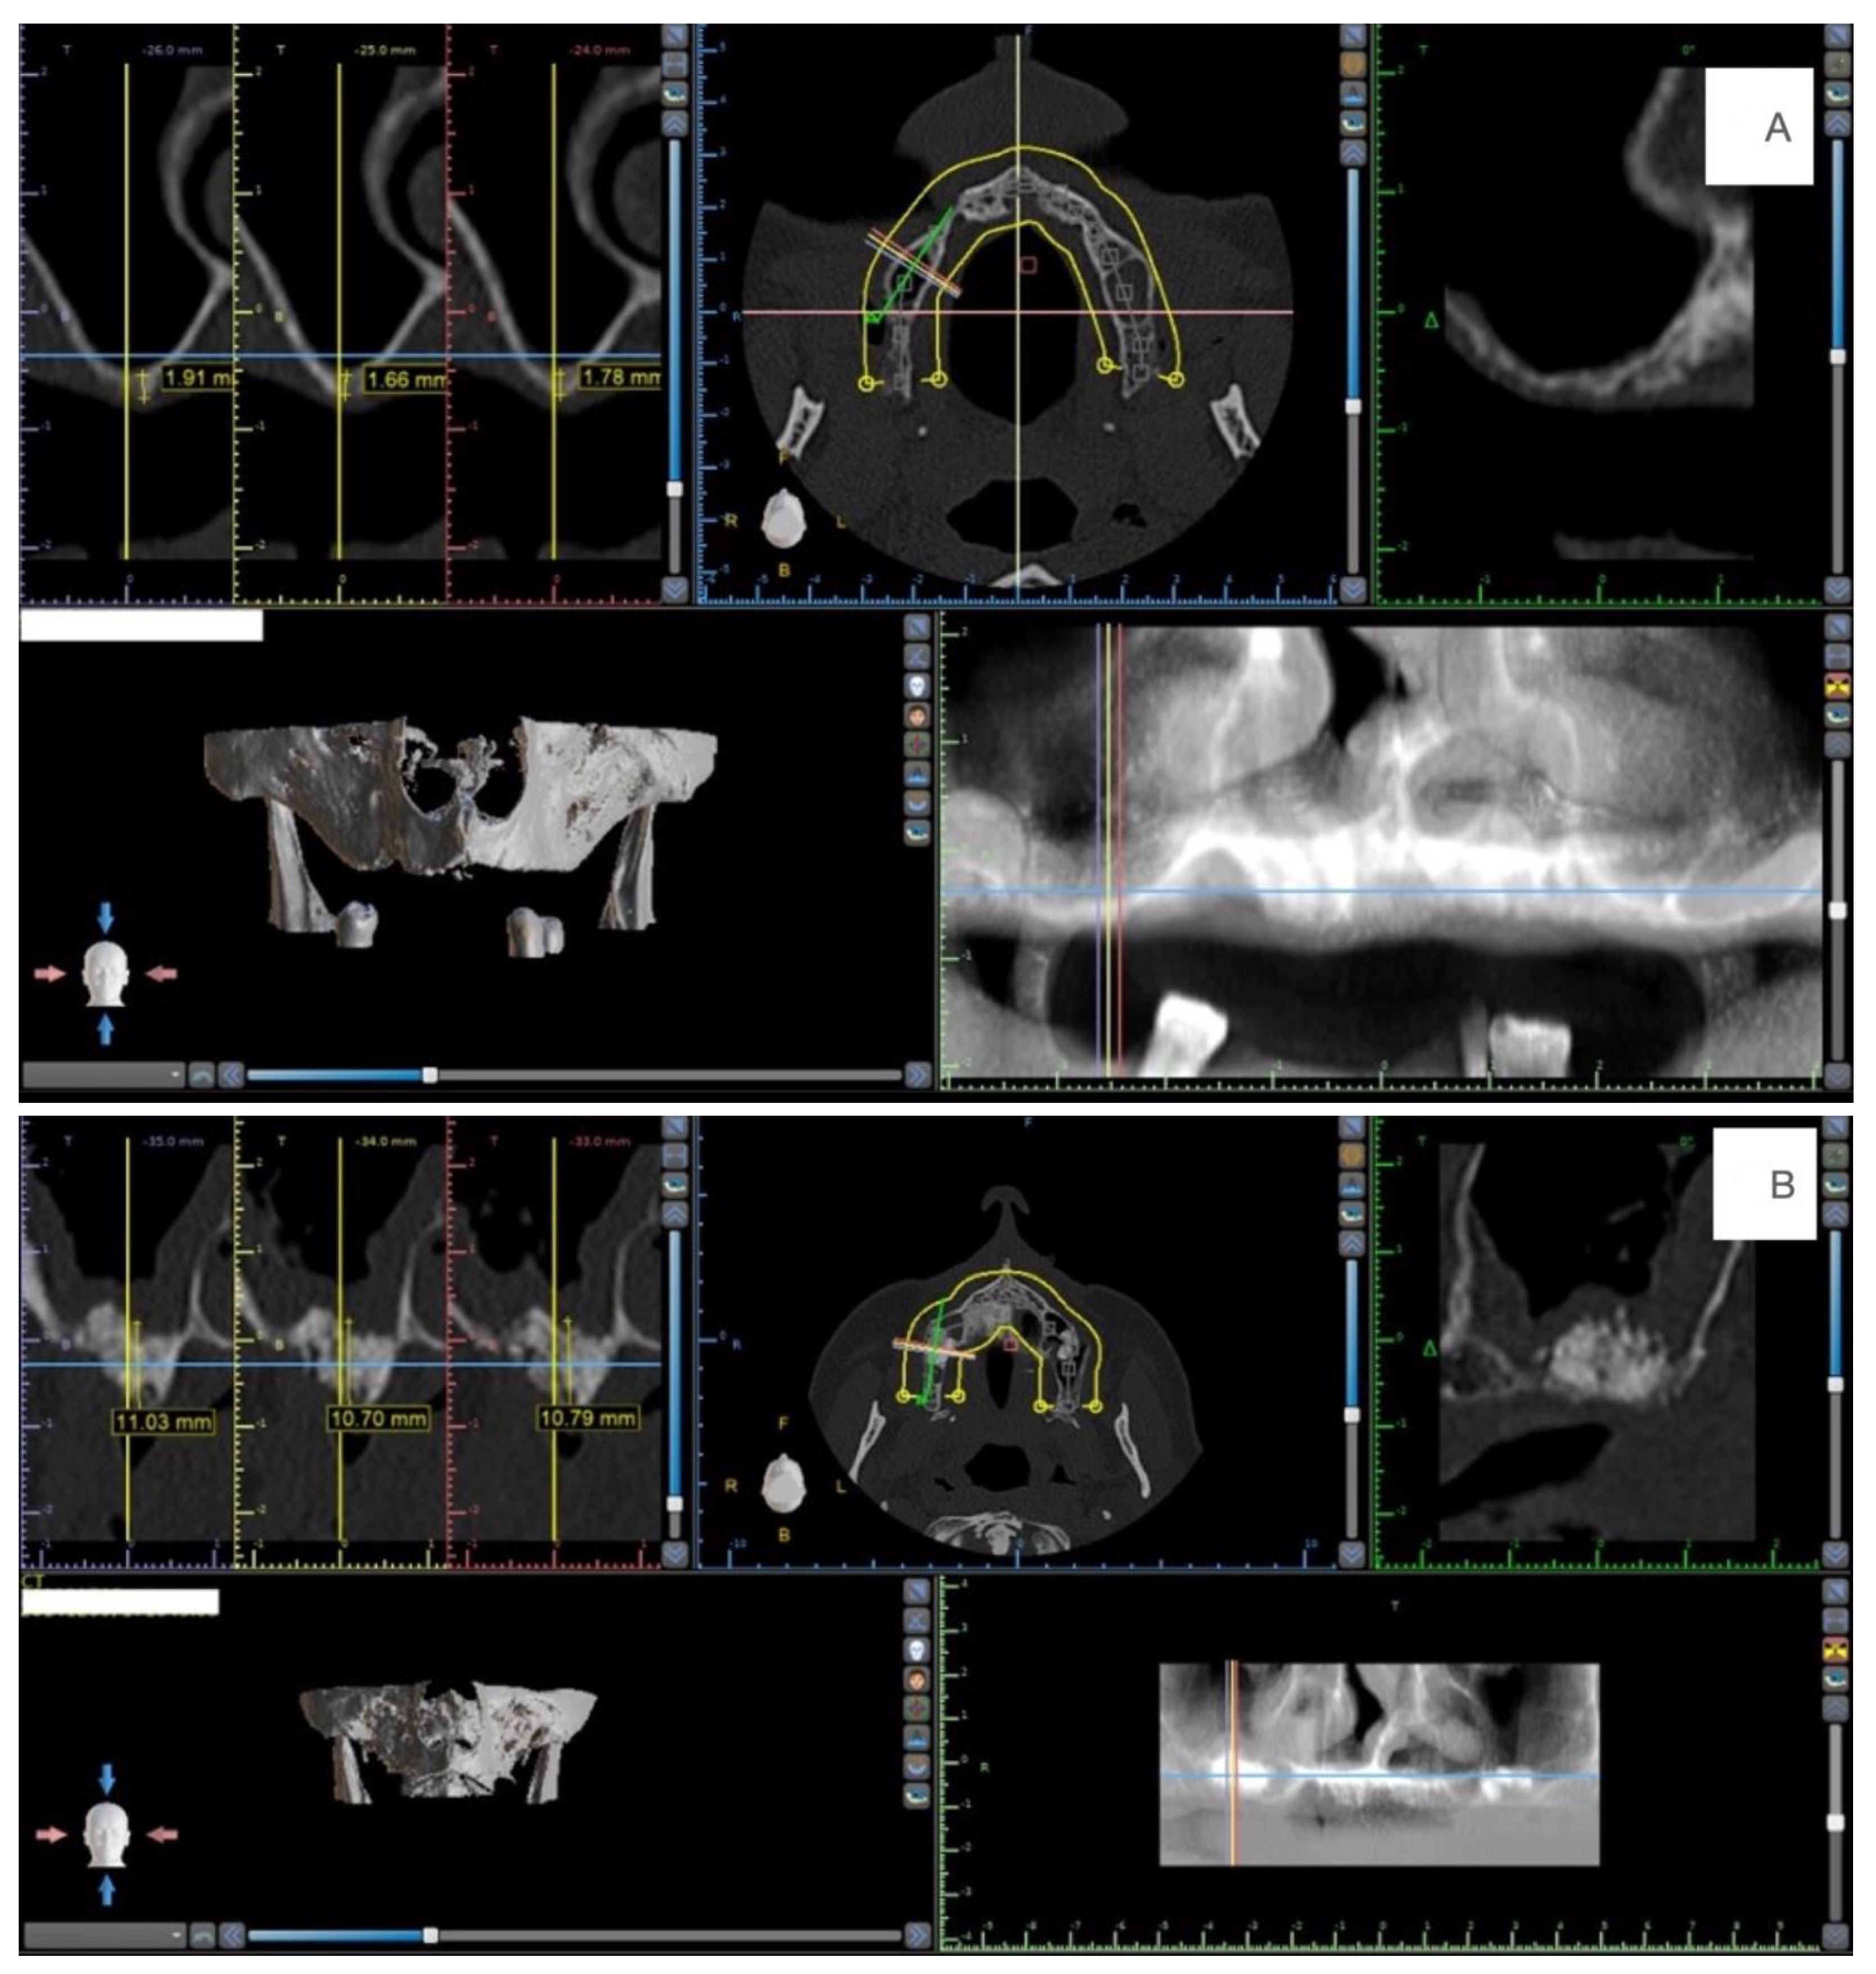

2.3. Radiological Analysis

3.2. Radiological Findings